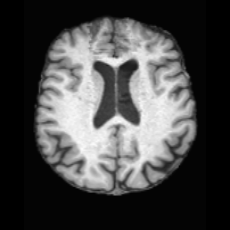

(a)PathologicalInput ImageSynthSR [18]Brain-ID [28]UNA [30]USBHealthyGround TruthRefer to captionRefer to captionRefer to captionRefer to captionRefer to captionRefer to captionRefer to captionRefer to captionRefer to captionRefer to captionRefer to captionRefer to captionRefer to captionRefer to captionRefer to captionRefer to captionRefer to captionRefer to captionRefer to captionRefer to captionRefer to captionRefer to captionRefer to captionRefer to caption(b)HealthyInput ImageConditionalLesion MaskUNA [30]USBRefer to captionRefer to captionRefer to captionRefer to captionRefer to captionRefer to captionRefer to captionRefer to captionRefer to captionRefer to captionRefer to captionRefer to captionRefer to captionRefer to captionRefer to captionRefer to caption

Figure 5: Comparison of bidirectional brain editing. (a) pathology-to-healthy, the circles and arrows highlight lesion regions and unsuccessful reconstructions; (b) healthy-to-pathology. Note that SynthSR and Brain-ID cannot perform healthy-to-pathology editing.

Pathology-to-Healthy Editing. Fig. 5 (a) presents comparison results on four input brain images with lesions of varying sizes, shapes, and densities. All competing models, although specialized for healthy brain image synthesis, struggle to reconstruct pathological regions, especially near lesion boundaries. In contrast, USB accurately reconstructs the corresponding healthy brain, even in challenging cases with large, high-density lesions where normal brain structures are almost completely obscured (last row). Tab. 2 provides a quantitative comparison for pathology-to-healthy editing, where USB achieves the best performance across all three datasets, demonstrating the effectiveness of its unified framework in reconstructing healthy brains from pathological inputs. Additional results are in Suppl. B.

Healthy-to-Pathology Editing. As shown in Fig. 5 (b), given a healthy brain image paired with a random lesion mask, USB seamlessly embeds the lesion into the healthy anatomy, producing realistic pathological appearances consistent with surrounding structural context. Yet UNA’s syntheses are visually unrealistic, with the conditioned lesion mask simply overlaid as a parallel layer onto the healthy brain. Tab. 3 further demonstrates USB’s superior performance. The evaluation was conducted on 100 pairs of lesion masks and healthy brains, with real stroke images